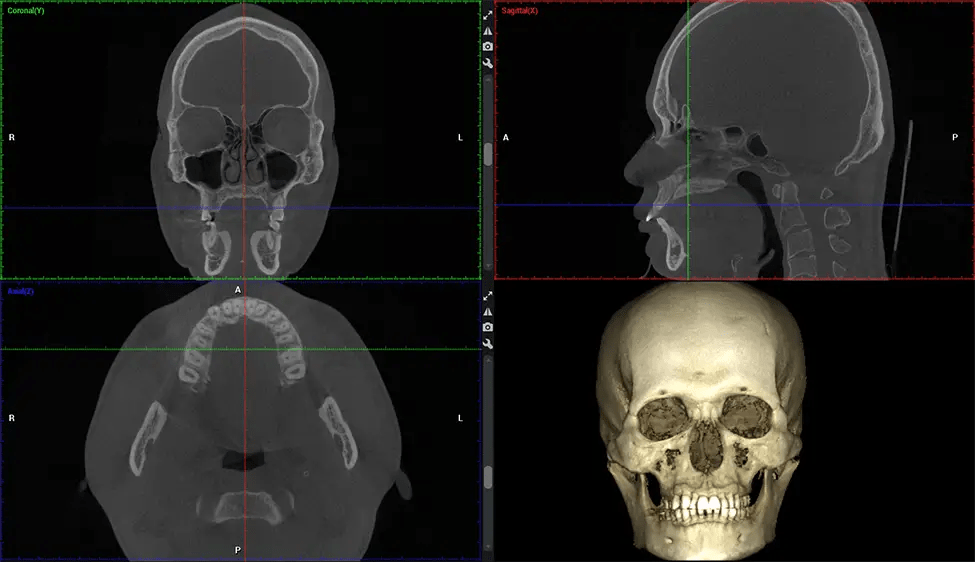

This 3D scan, called cone beam computed tomography, gives your dentist a more complete image of your oral anatomy and disease processes than a traditional X-ray. Unlike conventional X-rays, which capture a 2D image of your mouth from various angles, a 3D scan takes multiple digital X-rays for one image. It provides a complete view of your jaw, teeth, nerves, and soft tissues. This enhanced view allows dentists to detect minor issues not visible in traditional 2D scans, such as impacted wisdom teeth or bone fractures in the sinus cavity.

There are many benefits to using CBCT technology, especially compared to the traditional 2D X-ray format. One of the most significant advantages of CBCT scans is that they provide much more information than traditional X-rays. A scan lets your dentist see images from all angles of your jaw and mouth, including your sinuses, nasal cavity, cheekbones, and other surrounding areas. This added information helps your dentist craft a comprehensive treatment plan that addresses all aspects of your oral health.

After the scanning process, the captured X-ray images are processed by the CBCT software, which applies algorithms to reconstruct a detailed 3D image of the scanned area. The software compiles these individual X-ray images and creates a digital 3D representation of the patient’s anatomy. The reconstructed 3D CBCT image can be viewed and analyzed by the dentist or radiologist. This image can be manipulated, rotated, and zoomed in or out to examine specific structures and evaluate the patient’s condition.

Planmeca Viso G7 CBCT ( Cone Beam CT Scan ) is designed to surpass the demands of industry leaders, specialists, and large institutions. It’s has a large ø25×30 cm sensor with four built-in cameras. It can capture unlimited volume sizes from a ø3×3 cm to a ø30x30cm volume capturing the skullcap through C7 on the cervical spine. The Planmeca Viso G7 offers the industry’s largest single volume scan of ø30×19 cm. It’s poised to handle advanced imaging modalities such as Planmeca ProFace® and Planmeca 4D™ Jaw Motion technology. The occipital head support allows an unimpeded view of facial tissue.